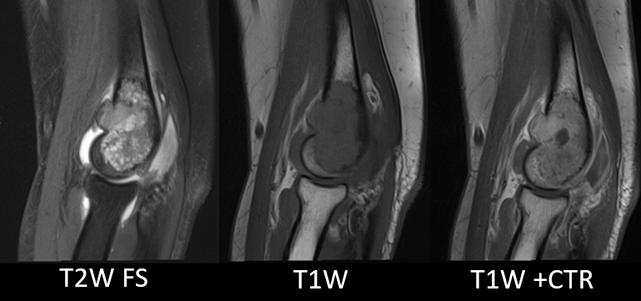

De diagnostiek van bottumoren kan complex zijn. Soms kom je een ossale laesie tegen als toevalsbevinding. Het is dan belangrijk de laesie adequaat te classificeren zodat de patiënt de juiste work-up krijgt of gerustgesteld kan worden. Voor deze karakterisatie en indeling zijn verschillende handvatten beschikbaar: Leeftijd, Locatie, en de Lodwick criteria. Afhankelijk van de leeftijd en locatie kan een waarschijnlijkheidsdiagnose worden opgesteld van mogelijke laesies. Tenslotte bieden de Lodwick criteria houvast voor het onderscheid tussen benigne, onzeker en maligne kenmerken. Het belangrijkste bij bottumoren is niet het labelen van de laesie met een specifieke diagnose, maar het duiden als benigne, lokaal agressief (deze groep kan benigne en maligne laesies betreffen) of maligne. Zo nodig kan worden verwezen naar een expertise centrum voor bottumoren voor een advies, de verdere diagnostische work-up en behandeling.